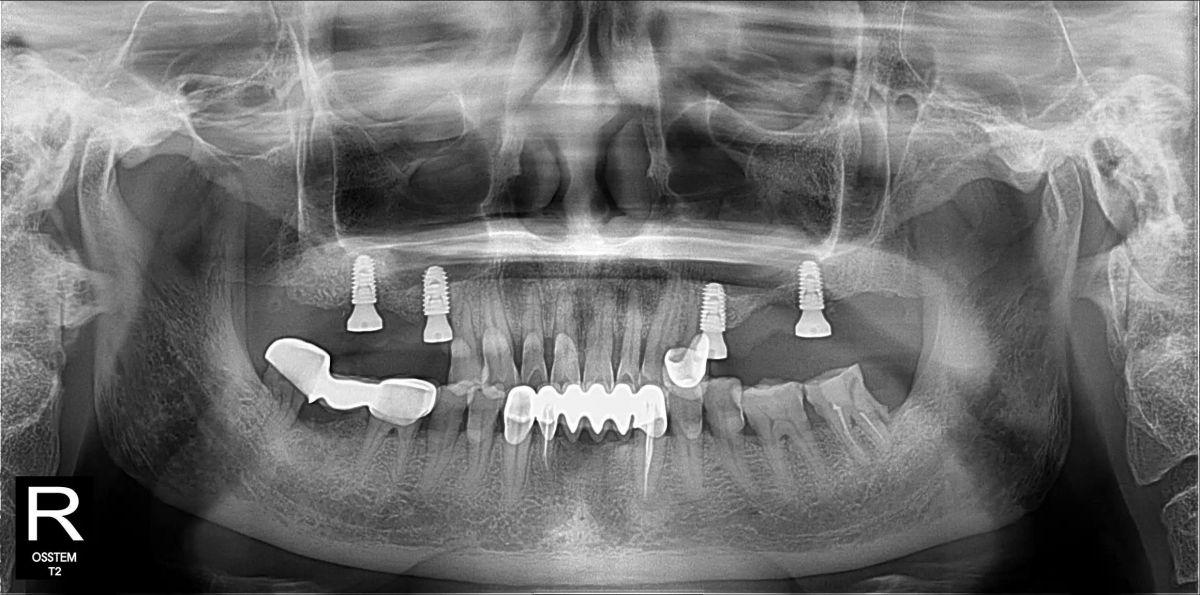

Sau khi đánh giá tổng thể và lập kế hoạch điều trị bằng công nghệ Hansafe, bác sĩ quyết định thực hiện phác đồ như sau:- Hàm phải: Implant tại R15 – R17, phục hình 3 răng, nâng xoang kín hàm phải

- Hàm trái: Implant tại R25 – R27, phục hình 3 răng, nâng xoang hở hàm trái

4 Kết quả thực tế sau điều trị:

Sau khi Implant tích hợp và lắp răng sứ hoàn chỉnh, chú Hòa đã:- Ăn nhai thoải mái các món yêu thích